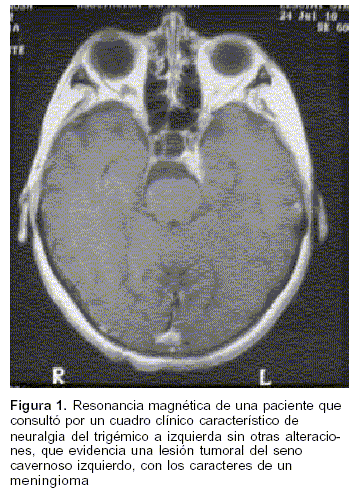

Otras entidades nosológicas que se presentan con el cuadro típico de la NT, y que constituyen las NT secundarias o sintomáticas, son procesos que comprimen el nervio o alguna de sus ramas, ya sean tumores (figura 1), quistes aracnoideos y más raramente aneurismas intracavernosos(5,7).

En las NT secundarias el dolor es provocado por alguna patología que afecte el nervio, tal como la compresión por un tumor o la afectación por esclerosis múltiple (figura 1).

La presentación clínica puede ser similar, incluso sin afectación de las demás funciones del nervio o de estructuras vecinas, por lo que es fundamental realizar siempre estudios imagenológicos, de elección una resonancia magnética, o en su defecto una tomografía.